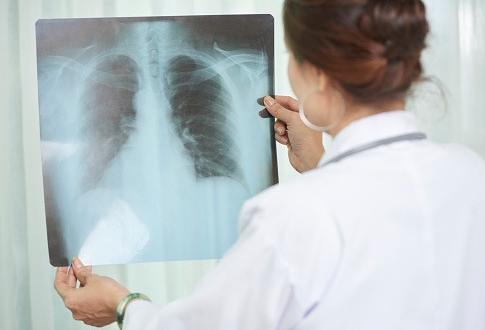

결핵은 신체 모든 부위에서 발생할 수 있는 병으로 그중 가장 흔한 것이 폐에서 발생하는 폐결핵 입니다. 결핵은 결핵균에 의한 만성감염에 의해 발생하는데 최근 1년 이내에 폐결핵에 감염된 적이 있거나, 에이즈, 규폐증, 만성 신부전 및 투석 당뇨, 위장 절제술 및 공회장 우회술 등의 수술력이 원인으로 발생 할 수 있습니다.

대부분의 결핵은 결핵에 걸린 환자가 기침 또는 재채기를 할 때 결핵균이 공기 중으로 나와 다른 사람의 폐포에 흡입되어 발생하게 됩니다.